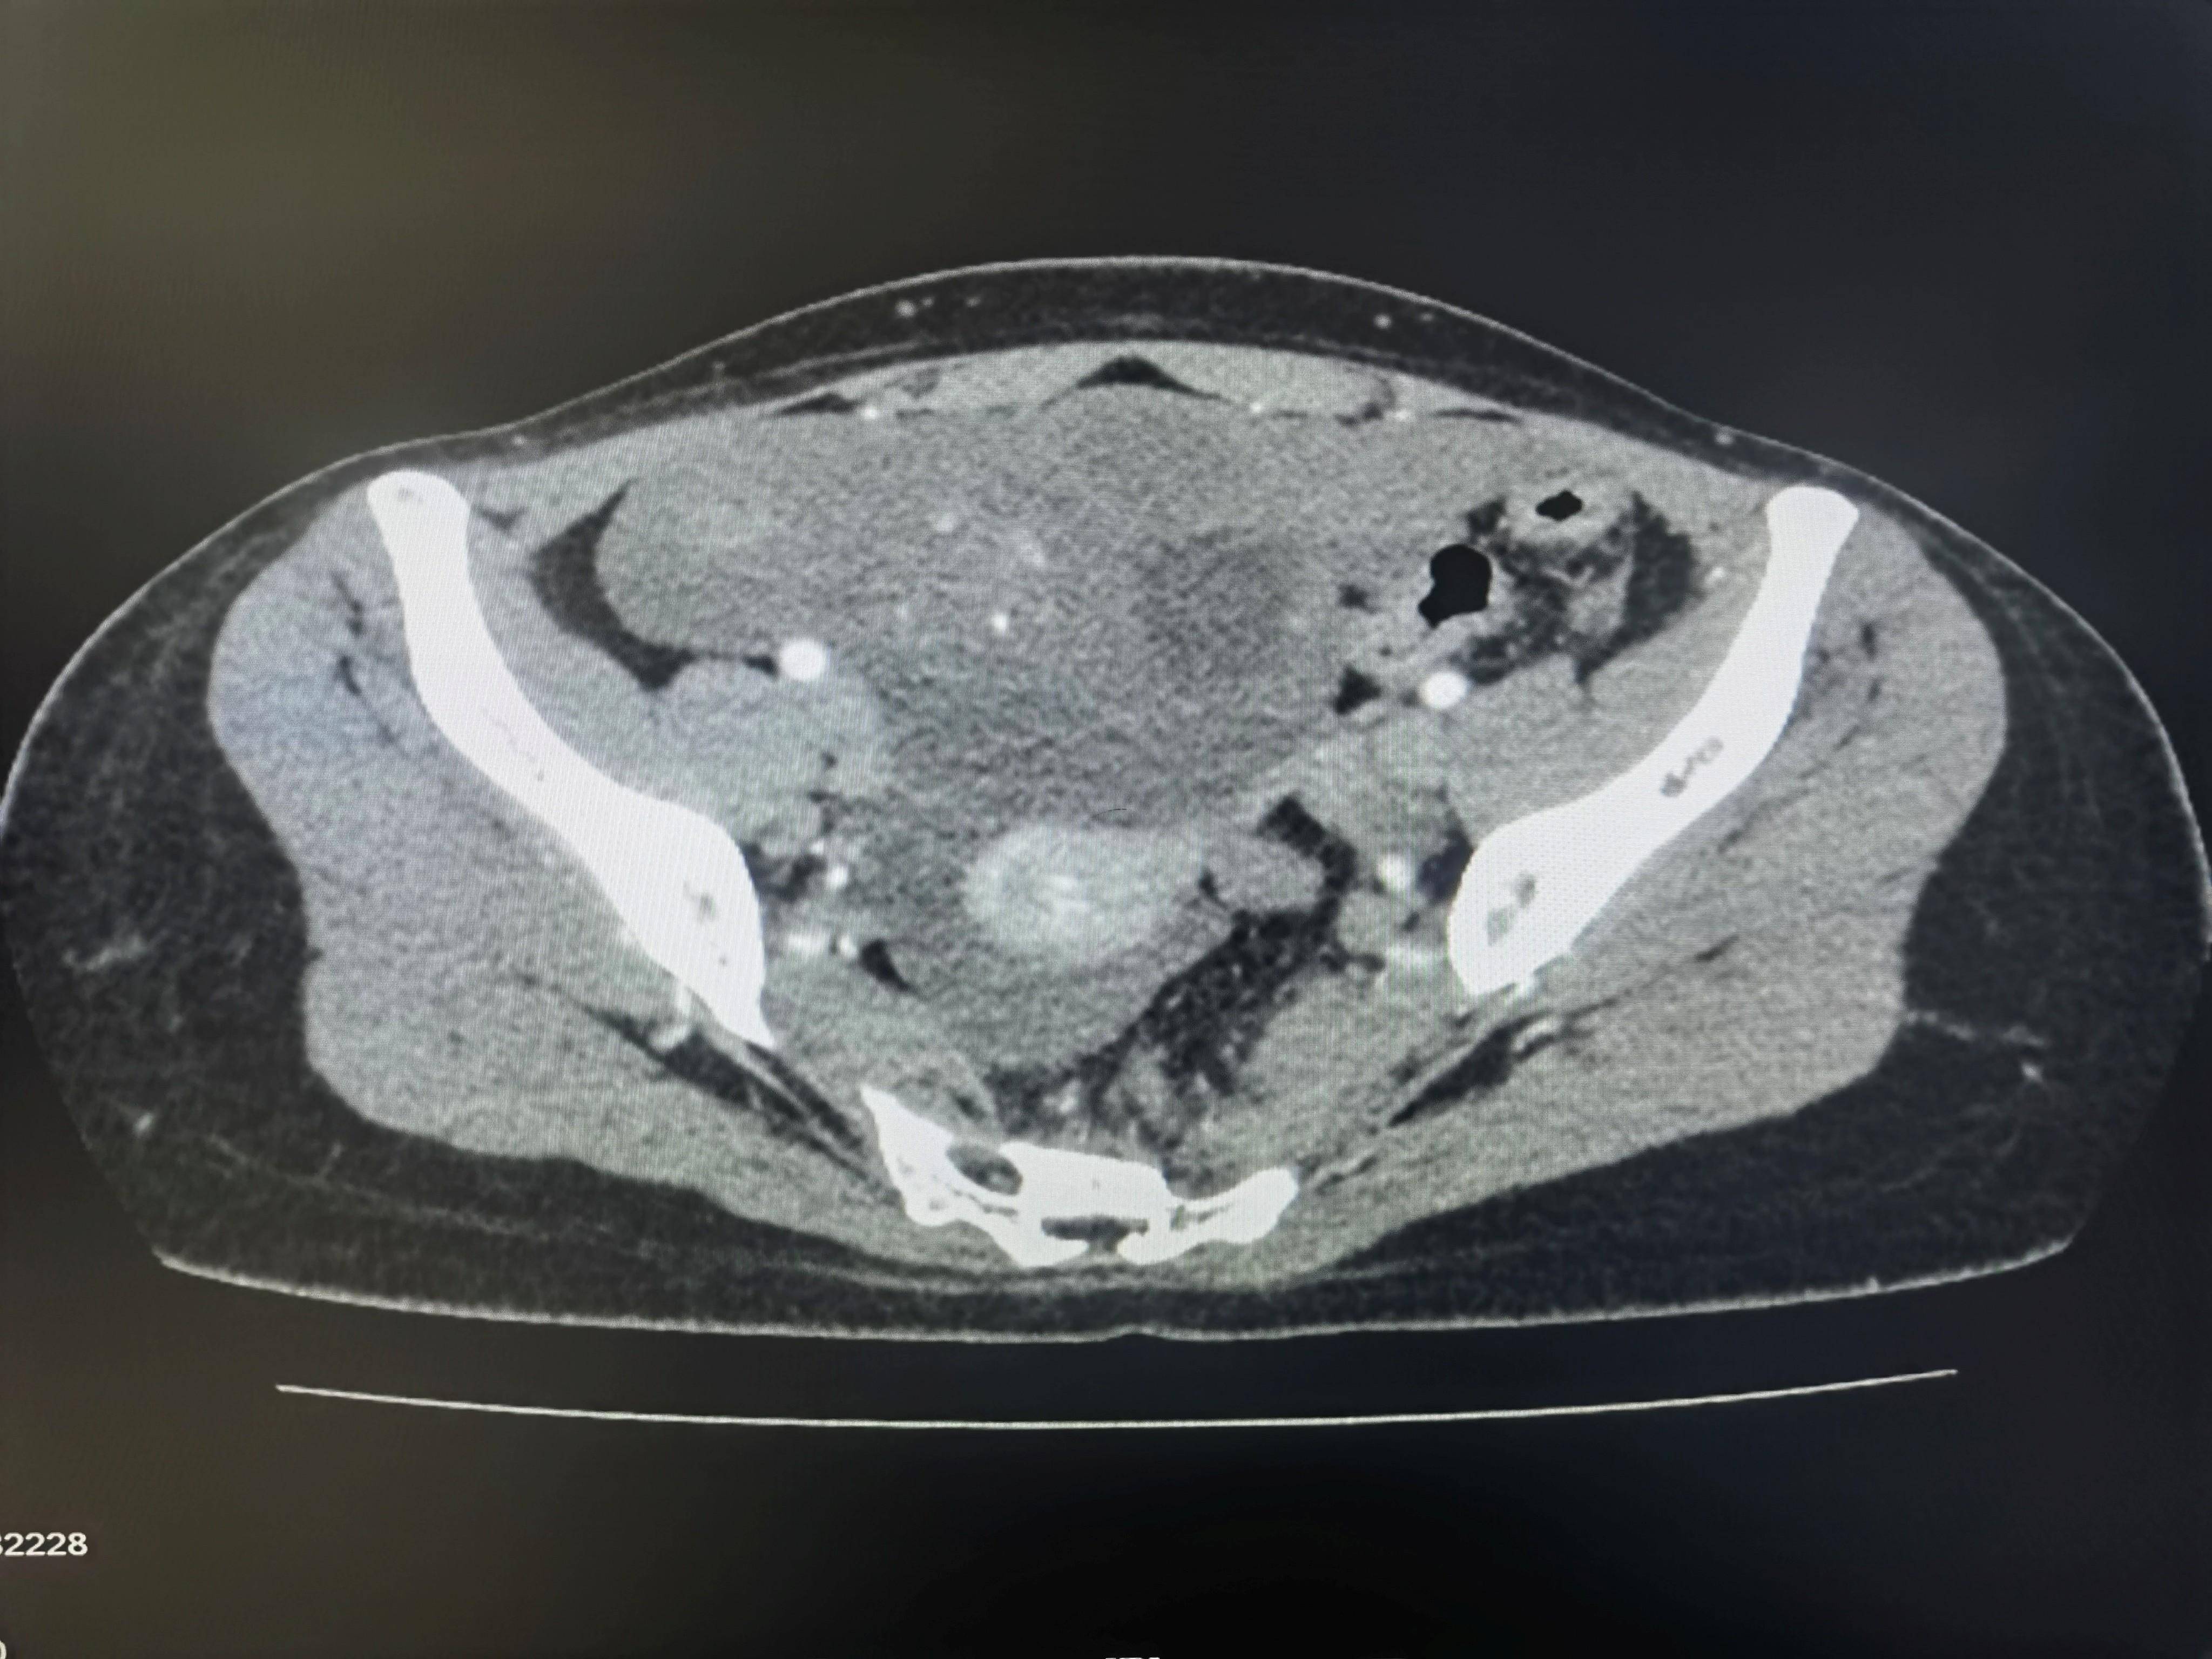

◈ 2021年7月8日,患者为求手术治疗就诊于我院门诊,行腹部CT检查提示:盆腔见不规则低密度影,包绕膀胱及子宫,与双侧附件及邻近肠管、右侧髂血管分界不清,三期CT值约为28Hu、27Hu、34Hu,其内密度不均,可见片状高密度影及钙化密度影。检查诊断:盆腔占位病变,考虑粘液瘤可能性大,建议进一步检查(因放射科无法获得胃肠间质瘤诊断及治疗病史)。结合患者病史及腹部CT结果,目前患者肿瘤包绕膀胱及子宫,与双侧附件分界不清。术中可能需要切除附件,因患者为年轻未婚未育女性,且直接手术的临床价值尚不明确,暂不考虑手术治疗。建议继续给予口服伊马替尼400mg QD。

2021年7月8日 腹部CT